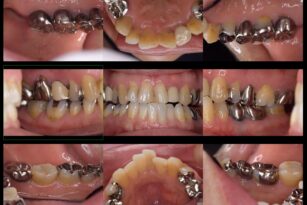

Before

After